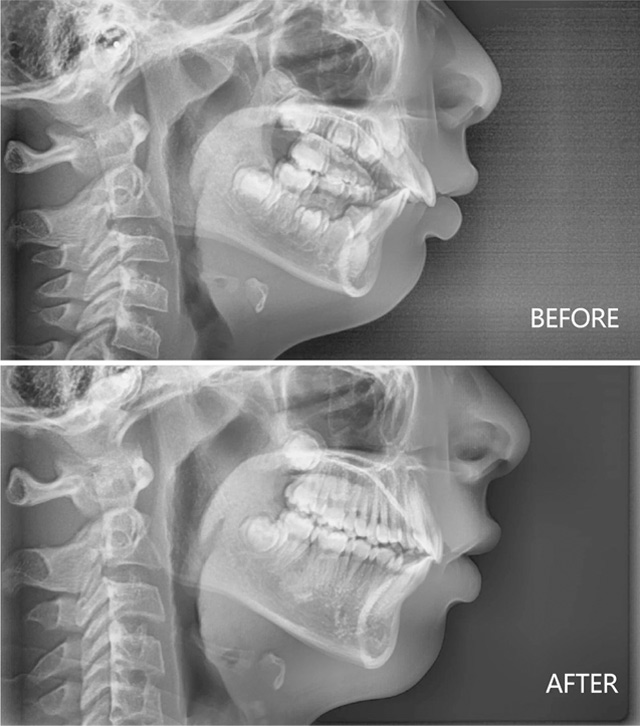

9岁女孩下巴后缩治疗前后

8岁男孩下巴后缩治疗前后